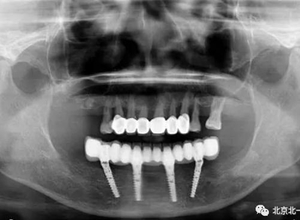

圖二十二:2015年到2016年復(fù)查時(shí)X片 ,有圖有真相

沒有假貨,貨真價(jià)實(shí),完成三年復(fù)查。

圖二十三:有圖有真相。

圖二十四:2017年11月復(fù)查時(shí)照片,植體很穩(wěn)定, 無骨吸收。